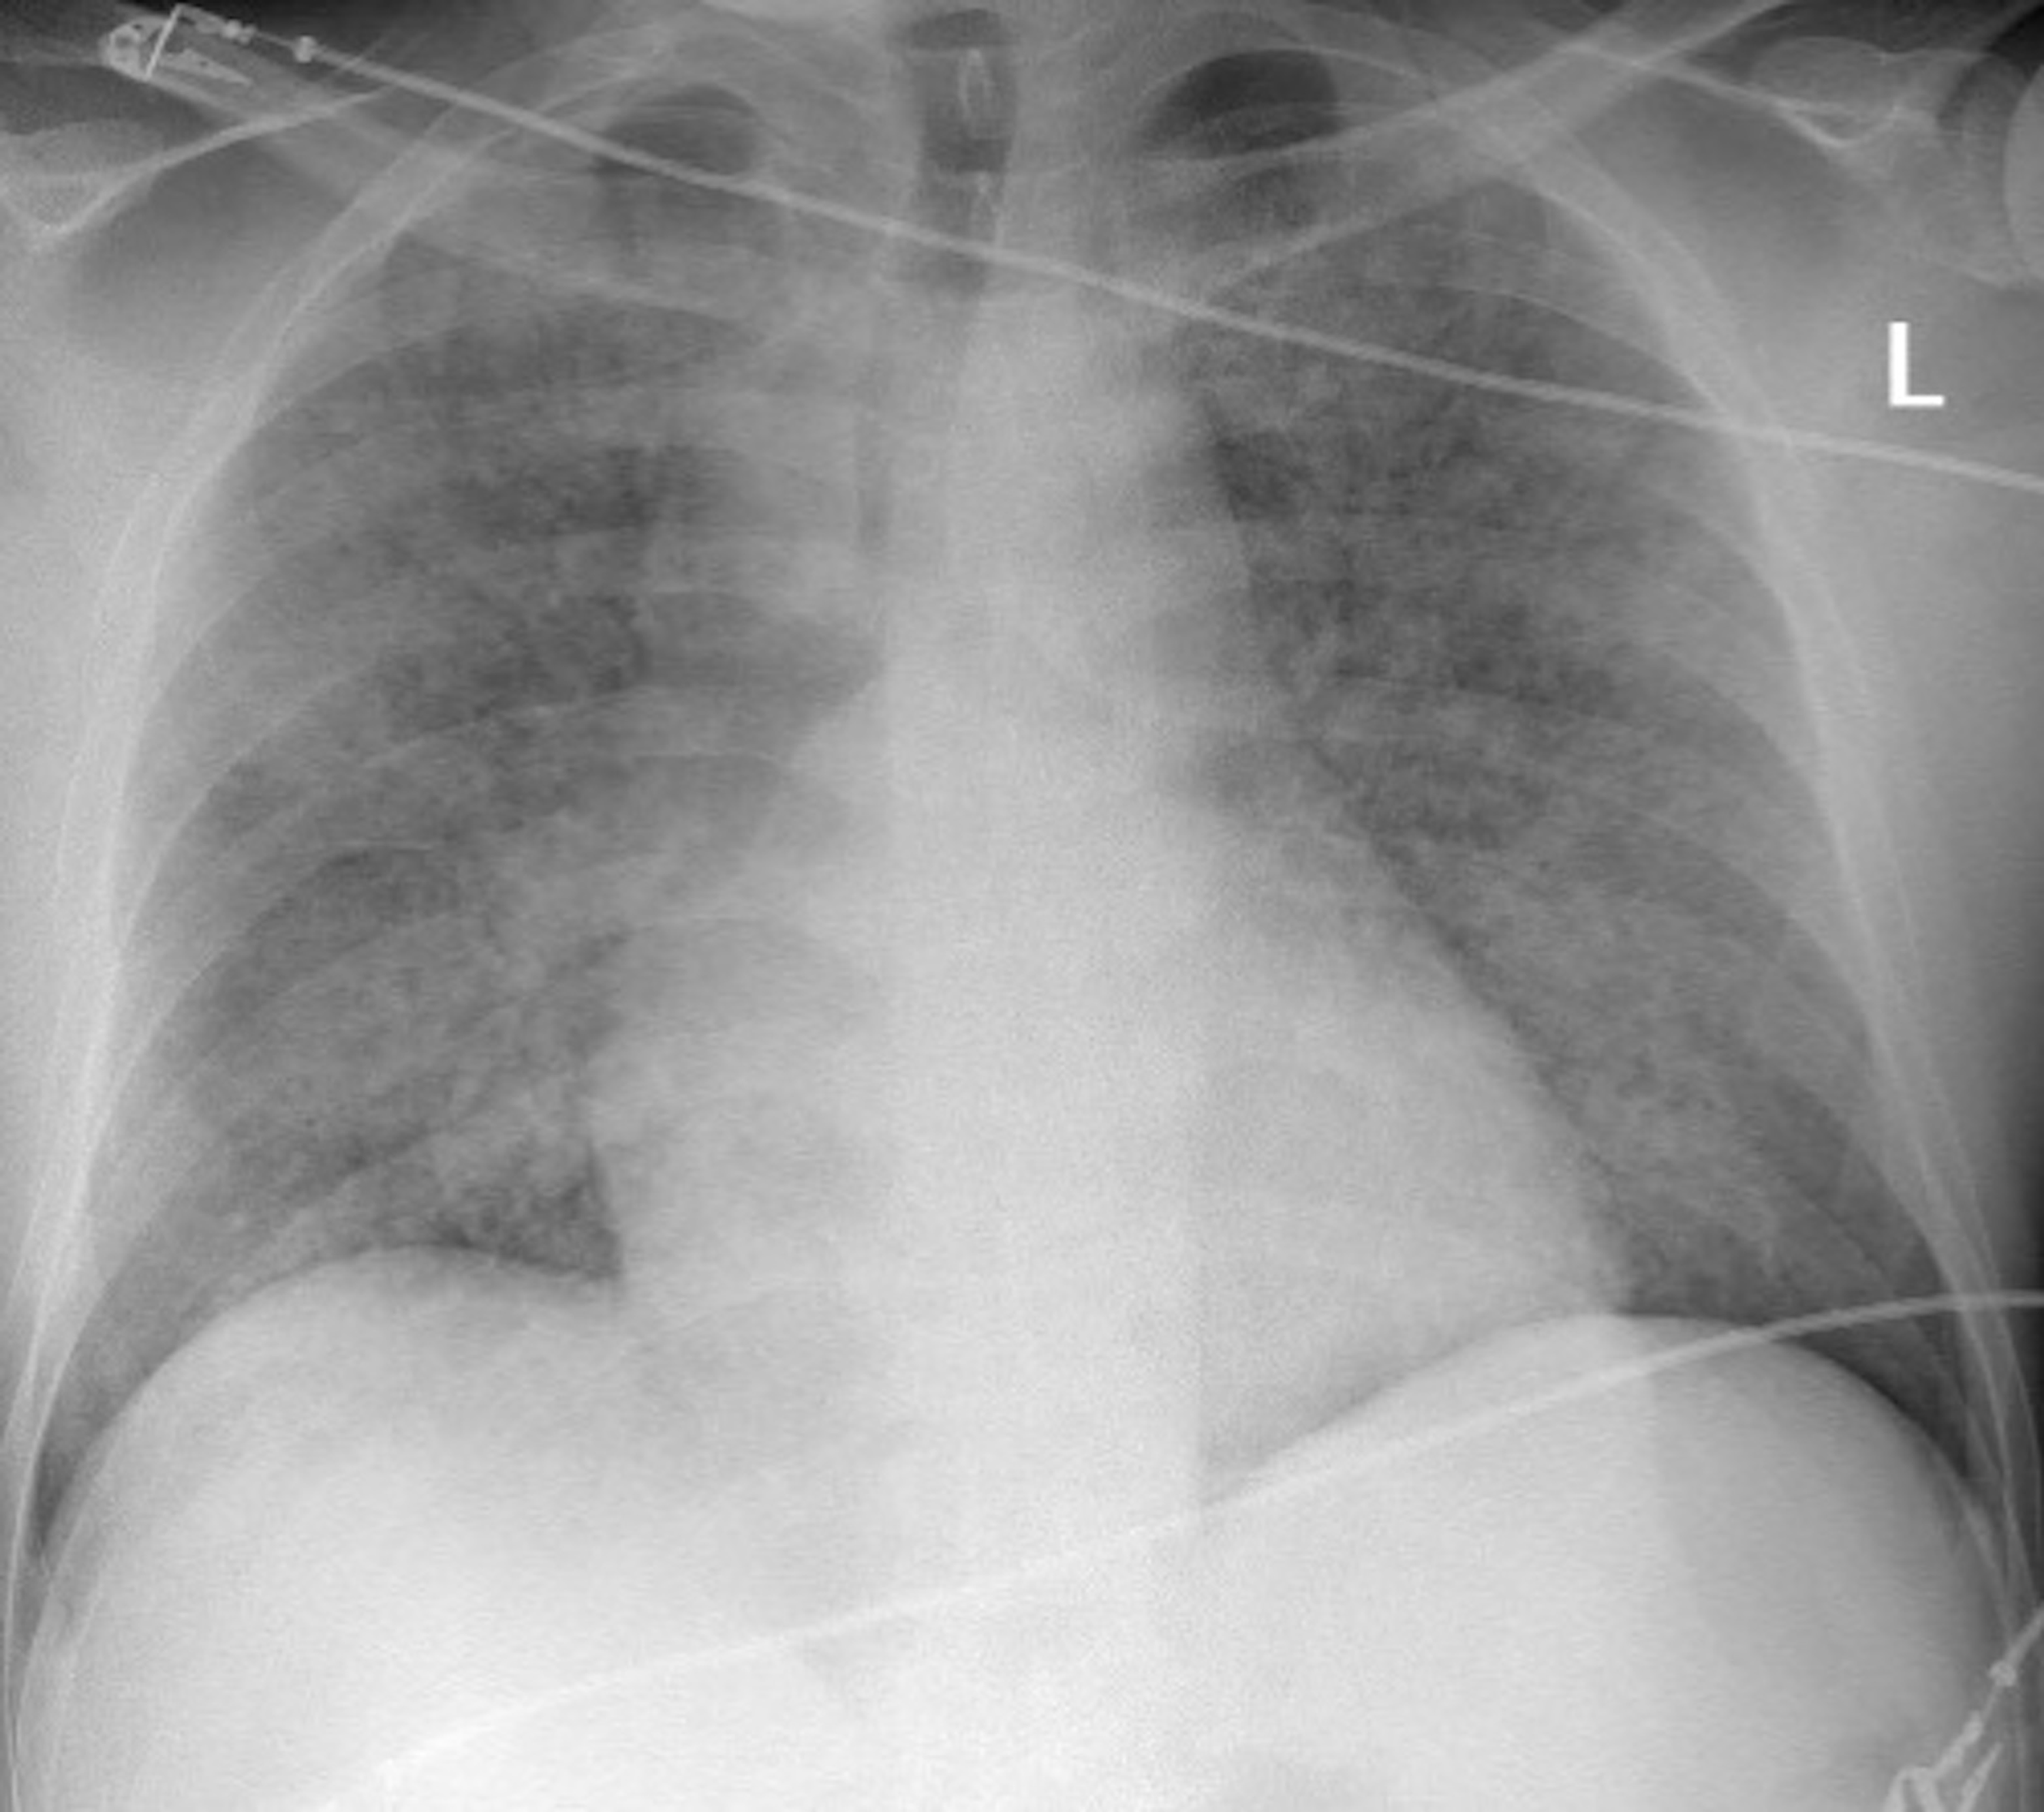

Pulmonary Hemorrhage X Ray Alveolar Hemorrhage learn about the causes, symptoms, diagnosis, and treatment of diffuse alveolar hemorrhage, a syndrome of pulmonary. learn about the causes, histopathology, and treatment of bleeding into the alveolar spaces of the lungs. learn about the causes, symptoms, diagnosis and treatment of diffuse alveolar hemorrhage, a syndrome of bleeding into. diffuse alveolar hemorrhage (dah) is a clinical. Alveolar Hemorrhage.